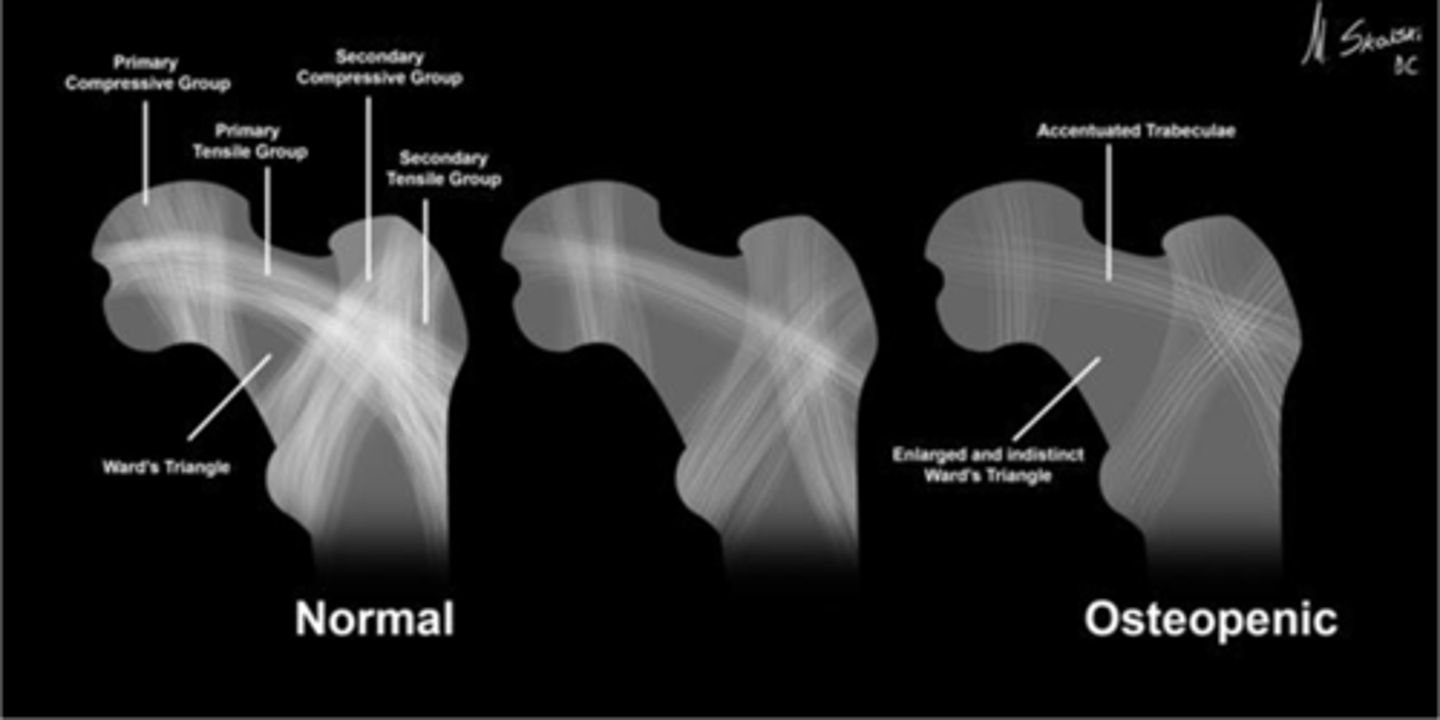

Wards triangle

An area that appears more radiolucent because it is surrounded by an abundance of trabeculae. The 1˚ and 2˚ compressive and tensile groups of the proximal femur leave a small region to appear more lucent

<p>An area that appears more radiolucent because it is surrounded by an abundance of trabeculae. The 1˚ and 2˚ compressive and tensile groups of the proximal femur leave a small region to appear more lucent</p>

Osteopenia

Wards triangle becomes enlarged as bone density reduces, signifying _____

<p>Wards triangle becomes enlarged as bone density reduces, signifying _____</p>